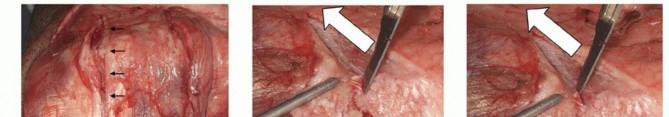

TECH FIG 3 • A. The triceps is split through its central tendon in line with the fibers. The tendinous portion is dissected from the olecranon to gain access to the ulna. B,C. To dissect the Sharpey fibers off the ulna, the surgeon uses the scalpel parallel to the ulna surface and maintains the release directly adjacent to the bone.(continued)

TECH FIG 3 •(continued)D. Comminuted distal humeral fracture in an osteoporotic elderly woman, with CT imaging confirming significant articular comminution. This is the view through the triceps split.